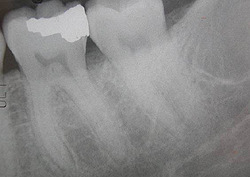

Зондування дна каріозної порожнини підтверджує наявність сполучення між каріозної порожниною і порожниною зуба. Електровозбудімость зуба з хронічним фіброзним пульпітом знижена, а рентгенологічний знімок підтверджує розрідження кісткової тканини біля верхівки кореня.

Хронічний гангренозний пульпіт клінічно проявляється болями в зубі під час прийому гарячої їжі або при впливі інших температурних подразників. пацієнти з гангренозний пульпітом скаржаться на рідкісні мимовільні болю і на неприємний гнильний запах з рота. В анамнезі є скарги на гострі болі нападів характеру з іррадіацією по ходу трійчастого нерва. Під час огляду зуба з хронічним гангренозний пульпітом виявляється, що каріозна порожнина широко повідомляється з порожниною зуба. Зондування каріозної порожнини хворобливо на всій глибині як коронкової, так і кореневої пульпи. Глибина ураження визначається ступенем поширеності пульпіту і, чим глибше ураження при гангренозний пульпіті, тим нижче ступінь електровозбудімості пульпи. О пів на випадках при гангренозний пульпіті на рентгенологічних знімках визначаються деструктивні зміни околоверхушечной тканини, ступінь вираженості деструкцій залежить від глибини пульпіту.

Пульпіт діагностують на підставі суб'єктивних скарг і інструментального огляду стоматолога . Під час інструментального огляду виявляється каріозна порожнина з розм'якшеним дентином, хвороблива реакція ураженого зуба на зміну температури. Перкусія при пульпіті майже завжди безболісна. Різка болючість спостерігається в місці, де каріозна порожнина максимально контактує з пульпою. Дані електровозбудімості ( електроодонтодіагностика ) і рентгенологічні дослідження дозволяють уточнити характер і глибину пульпіту.